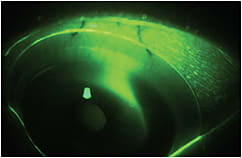

To check for haptic misalignment, apply fluorescein to the surface of the lens, then watch behind the slit lamp to see where it rapidly uptakes under the lens (Figure 2). If not addressed, this may lead to debris entrapment under the lens, resulting in symptoms of cloudy vision (Figure 3). This problem can be remedied by using a toric or quadrant-specific haptic design.